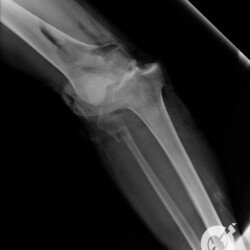

Fratura da patela com importante desvio e fratura cominutiva do 1/3 proximal da tíbia comprometendo a eminência intercondiliana.